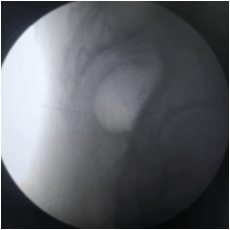

This procedure is performed with the patient in a prone position on the Operating table. Some practitioners like to prepare patients with laxatives the night before. With fluoroscopic guidance, a thin spinal needle is advanced through the sacrococcygeal hiatus. Needle placement is confirmed and dye spread is checked under fluoroscopy. Medication is delivered at the site of the Ganglion of Impar. This helps in blocking the sacrococcygeal plexus of nerves.

AP View

Intraop fluoroscopy image

of ganglion impar injection